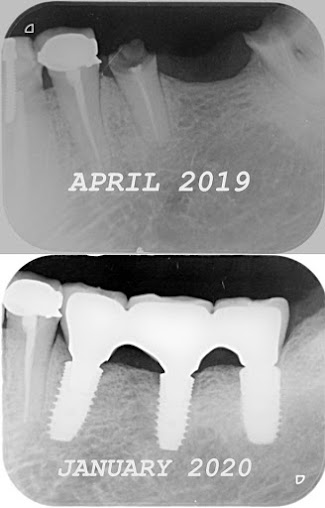

About Dr Joglekars Dental Solutions We are a 23 year old practice at Chinchwad. We take care of our patients for all types of dental problems.We perform --- Family dentistry Orthodontics and clear alignersMicroscope dentistry DIgital smile design Intraoral scanners 3D X ray / CBCT scan Microscope root canal treatment Complete dentures, Implant supported dentures

Dental Implants $349